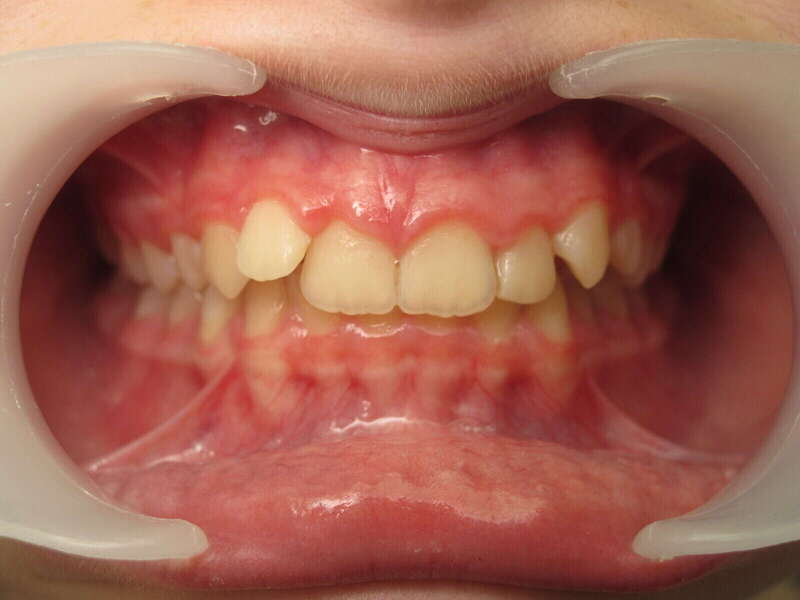

Cas n°1 traité par aligneurs (interception) - enfant

Ce cas d’interception chez un enfant de 8 ans démontre l'efficacité des aligneurs pour corriger des troubles fonctionnels précoces. Le diagnostic présentait des inversions d'articulé provoquant une déviation de la mandibule vers la gauche et un décalage des milieux.

Grâce à une coopération exemplaire et un traitement totalement indolore, l'expansion de l'arcade a permis de recentrer la mâchoire. Cette intervention a littéralement remis la croissance sur les rails, neutralisant le risque d'asymétrie faciale squelettique.

Avant